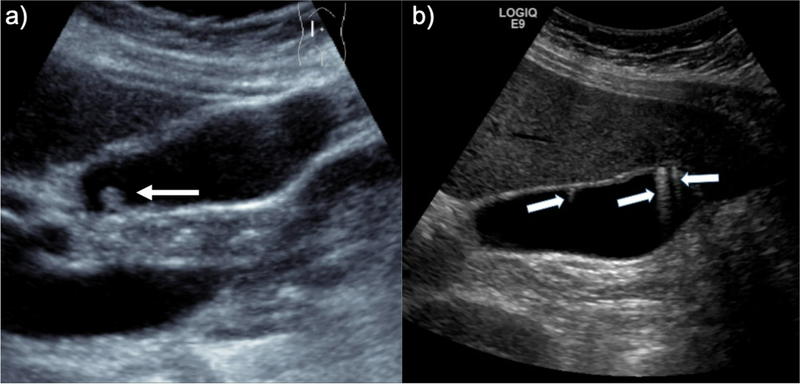

Khi thực hiện siêu âm, túi mật thường có hình dạng giống quả lê và thường chứa một lượng dịch mật. Thành của túi mật bình thường thường hiển thị rõ ràng và có độ dày nhỏ hơn hoặc bằng 3mm (≤3mm). Sự đo lường chính xác nhất thường được thực hiện ở phần thành phía trước của túi mật trên trục dọc khi sóng siêu âm phát ra vuông góc với thành của túi mật. Ở trạng thái bình thường, túi mật ở người trưởng thành có đường kính từ trước đến sau từ 8 đến 12cm và chiều ngang nhỏ hơn hoặc bằng 4cm (≤ 4cm).